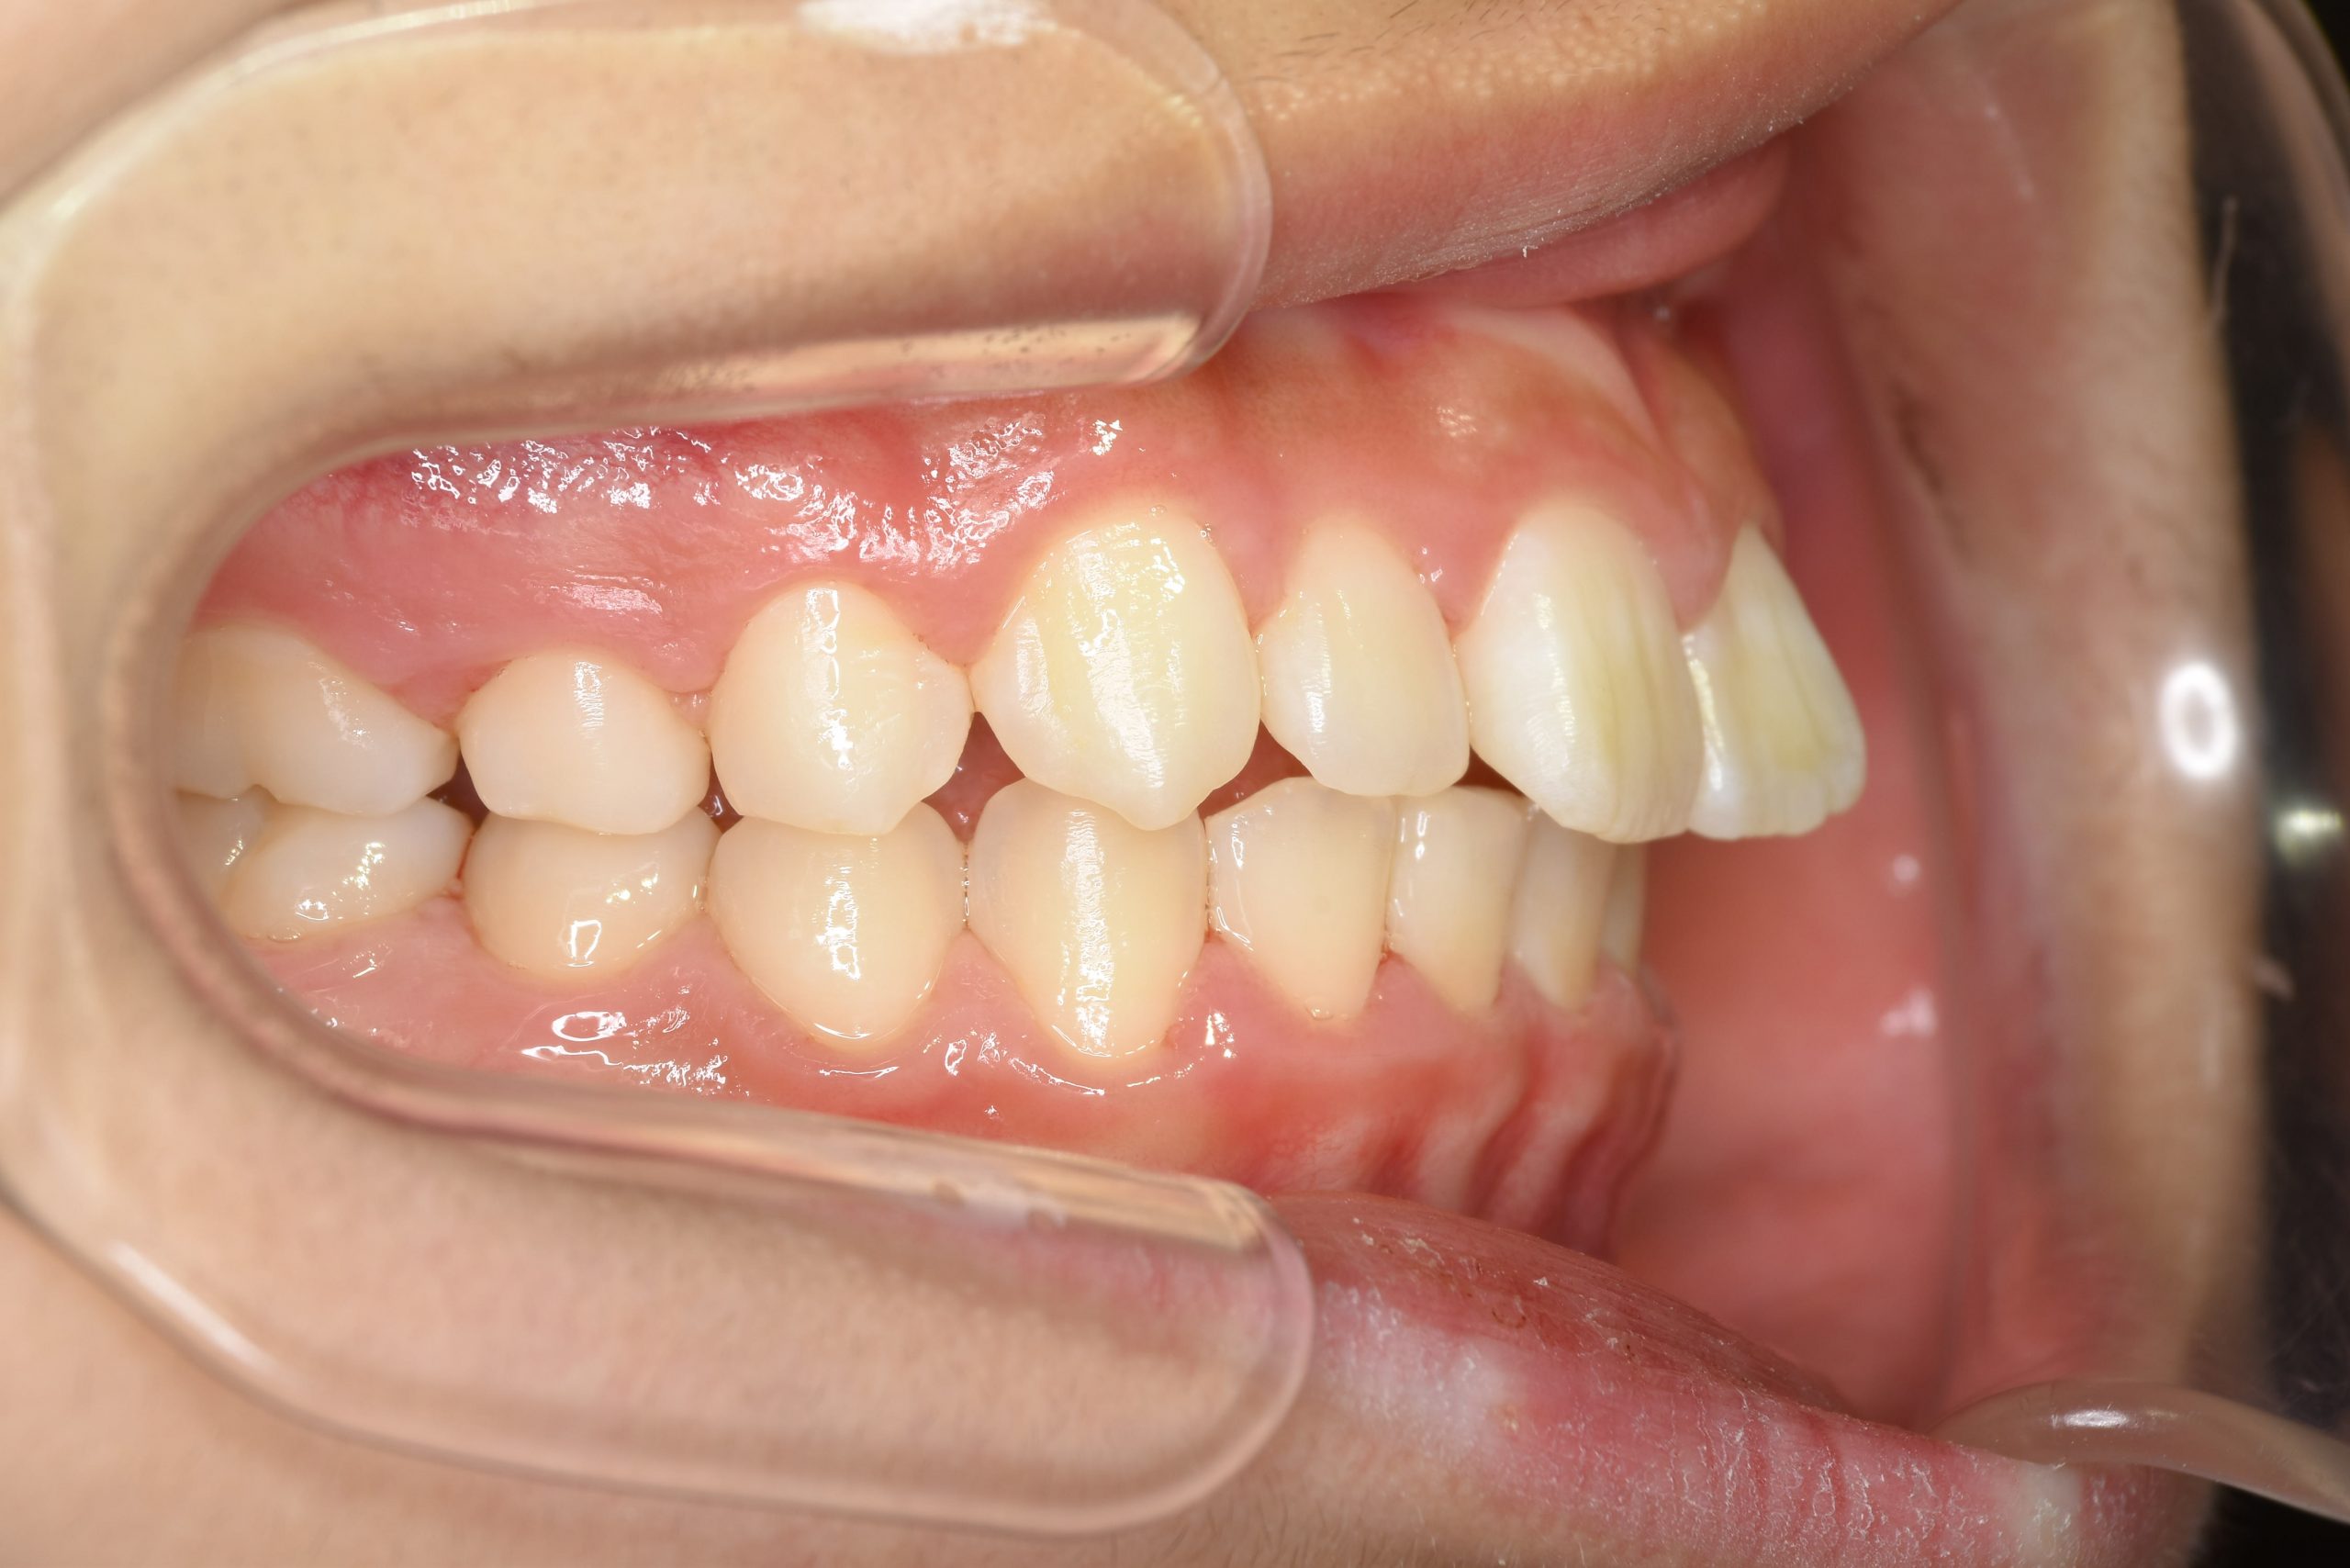

アフター

全顎ワイヤー矯正 症例_218